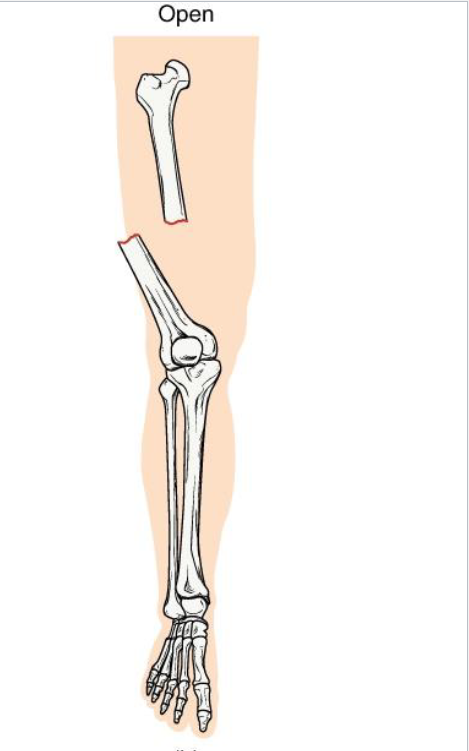

Open Fracture

<p><strong>Definition:</strong> Bone <strong>breaks through the skin </strong>(or skin is broken, exposing bone)</p><p><strong>Mechanism: High-energy trauma </strong>(ex: motor vehicle accident, gunshot)</p><p><strong>Clinical note: High infection risk and delayed healing.</strong></p><p><strong>Key concept</strong>: Requires surgical cleaning and fixation</p>